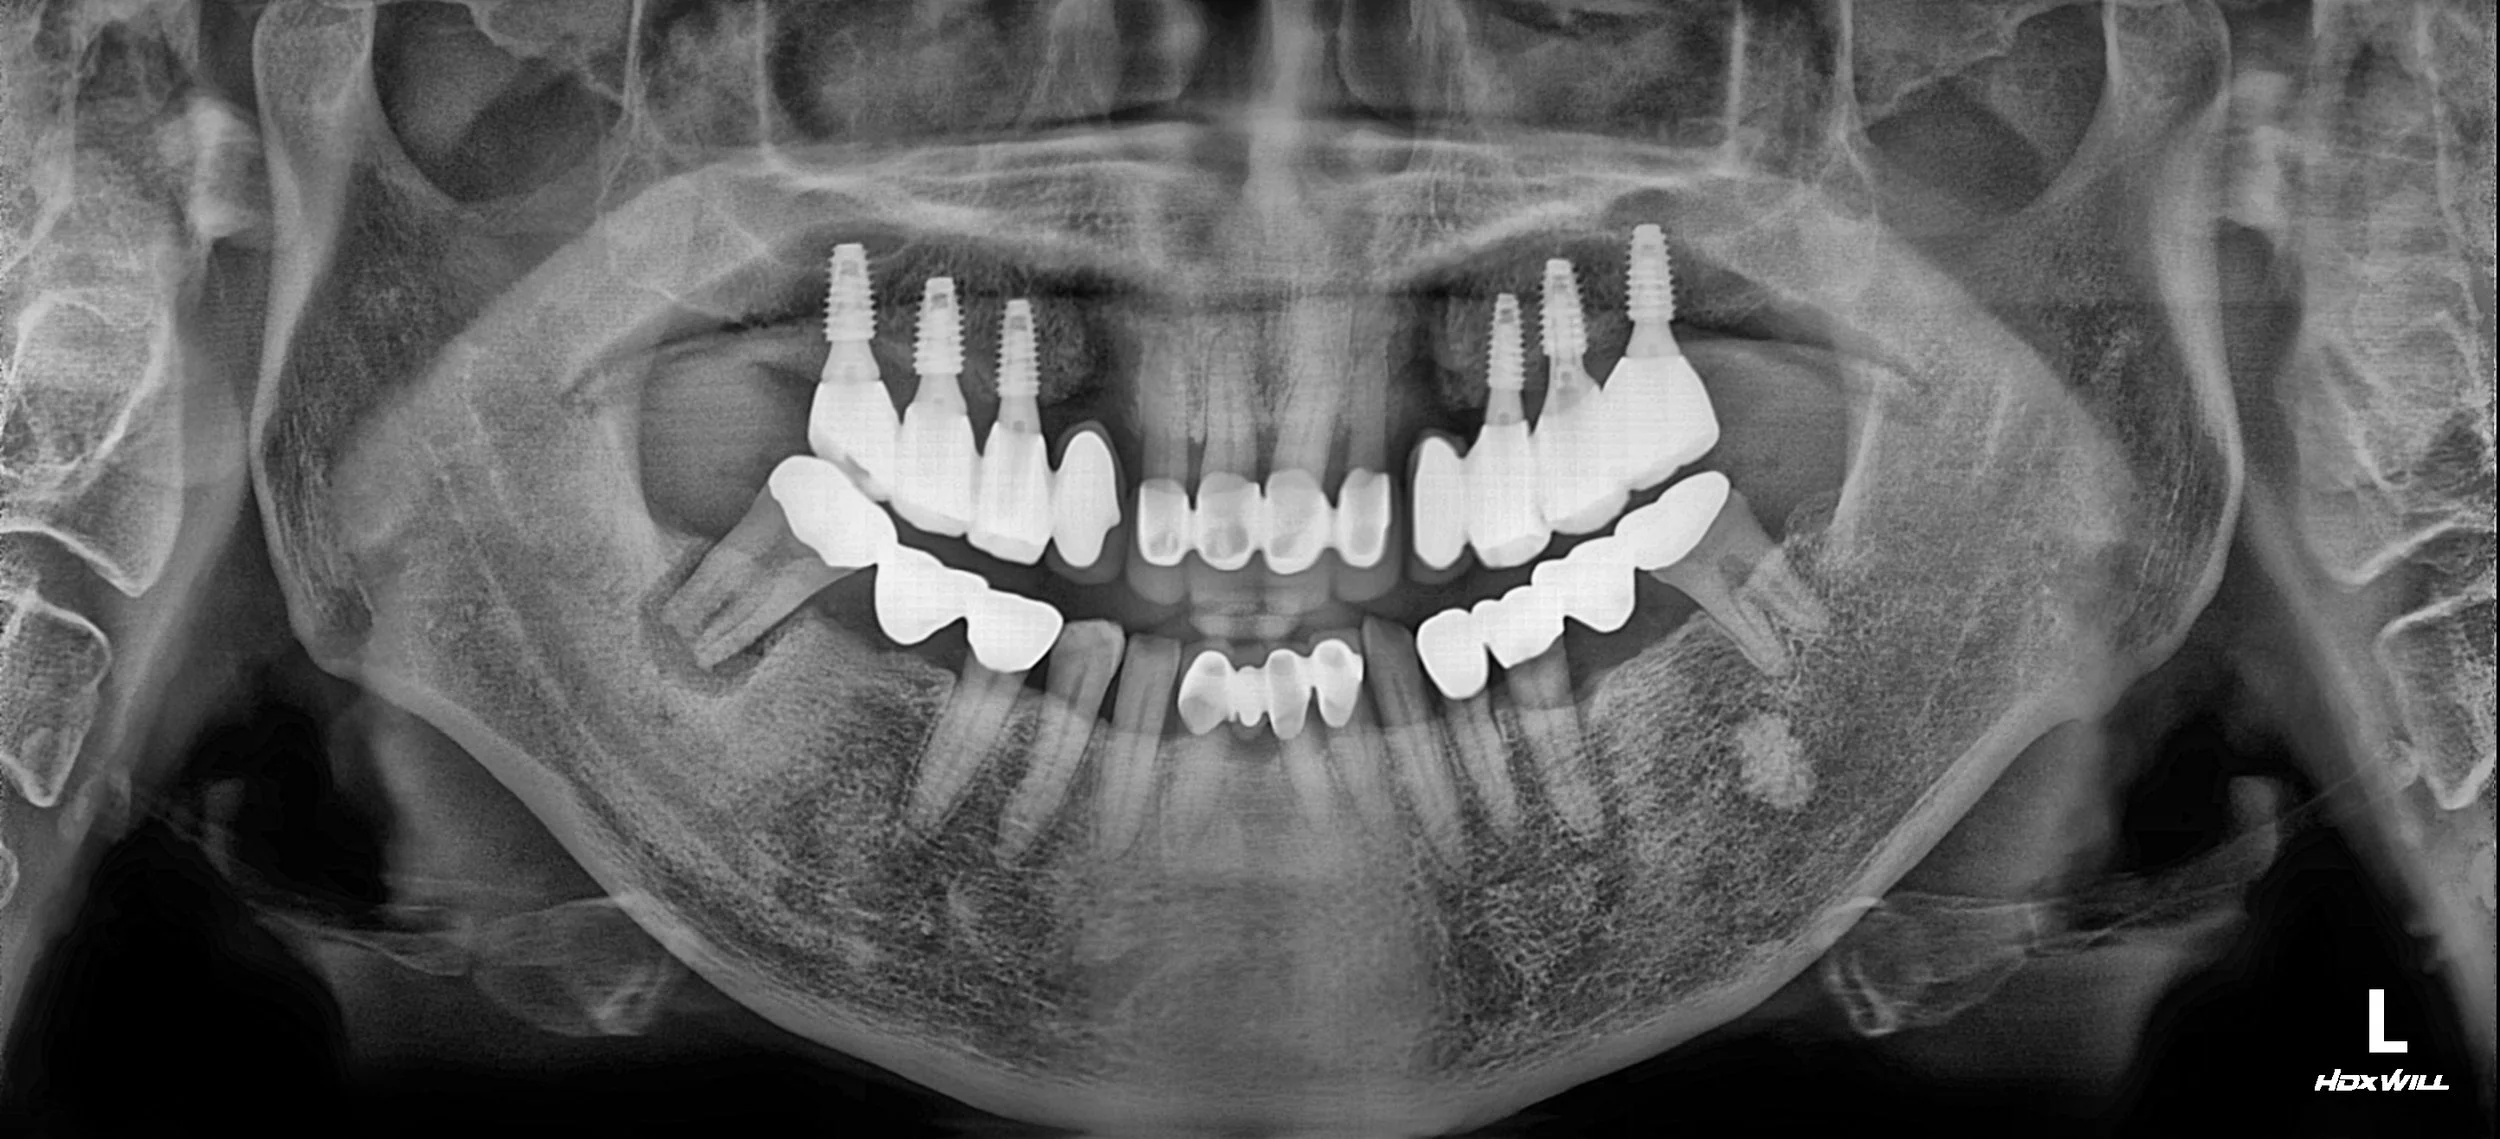

2. Implant Surgery: Dental implants were strategically placed in the maxillary and mandibular posterior segments to provide a firm foundation for the new occlusion.

3. VDO Management & Realignment: The occlusal vertical dimension was elevated. This provided the necessary clearance to properly align the mandibular anterior teeth, effectively addressing the previous lingual displacement.

4. Final Prosthetics & Clinical Observation: Precision-milled, implant-supported bridges were delivered. A notable observation during this phase was that once the stable occlusion was established, the pre-existing issues in the non-functional 40s quadrant (lower right) became more clinically prominent. While these teeth were not part of the primary functional unit previously, the new occlusal scheme highlighted the need for future intervention.

5. Phased Planning (Financial Consideration): Although further treatment for the 40s quadrant is indicated, the procedure has been deferred at the patient's request due to financial constraints. The case currently remains in a stable, functional state with a planned "maintenance and monitoring" approach for the lower right segment.